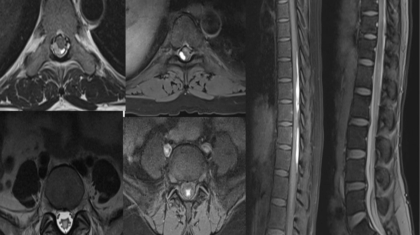

56 female

Acute onset severe headache – holocranial- thunderclap type while bathing with no postural variation. Recurrent vomiting and neck stiffness.

Prior H/o disabling migraine attacks